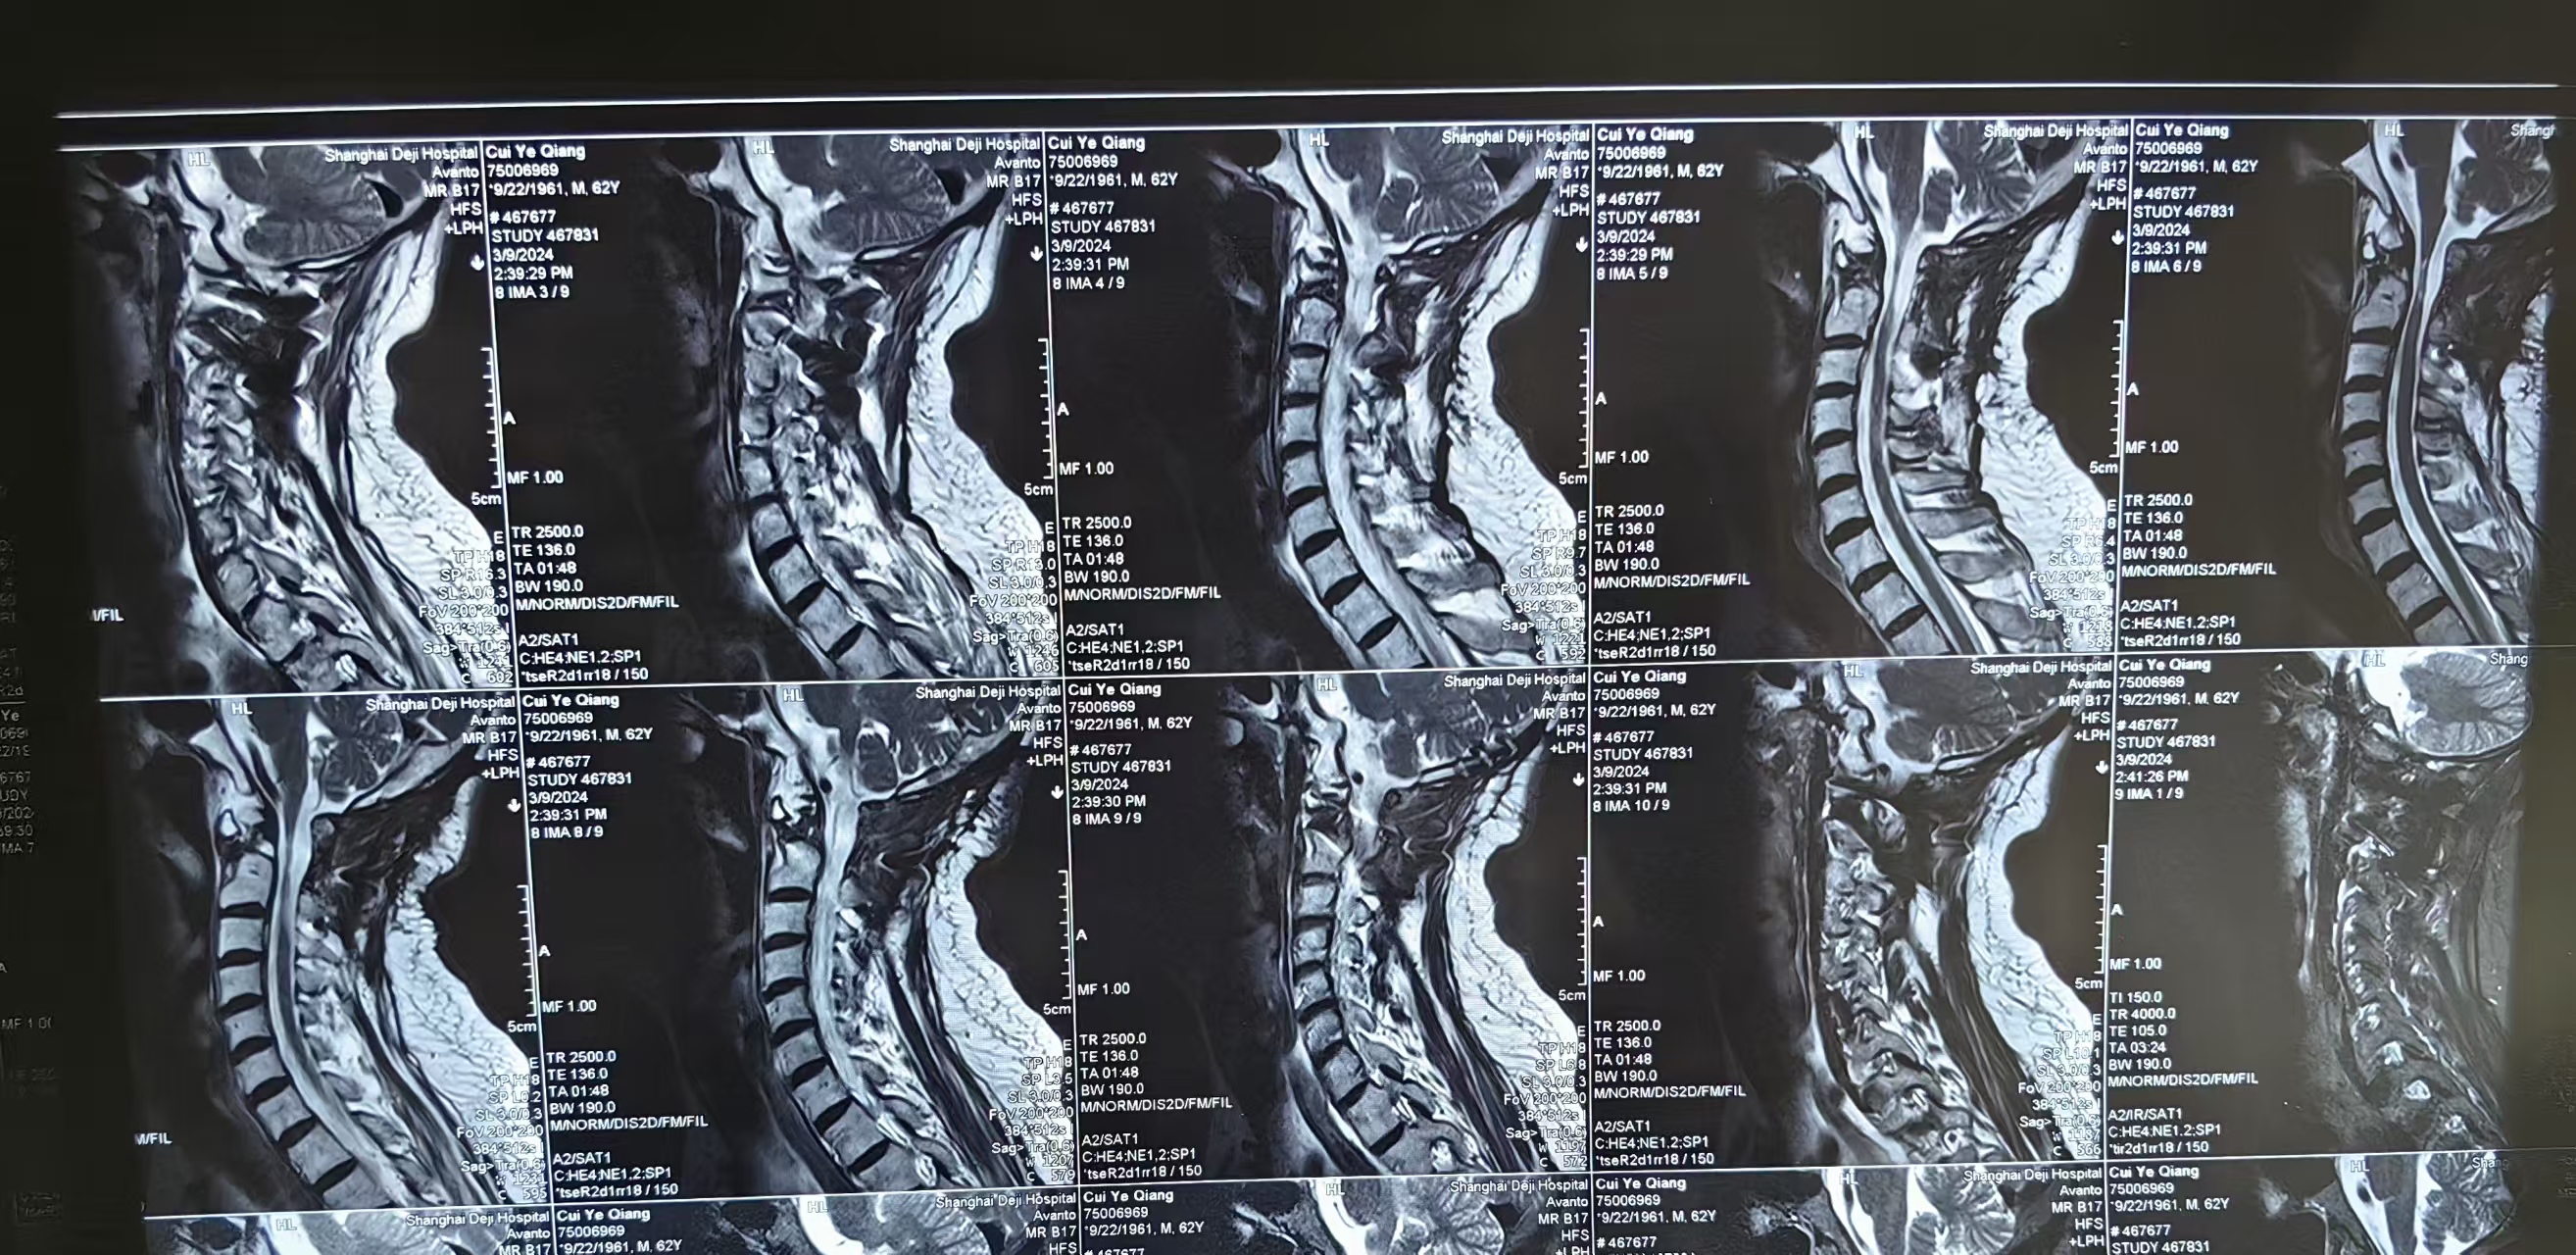

• 2024.03.09,复查,对位良好,但术前症状难以恢复。

• 日期:2023.11

• 主刀:王超